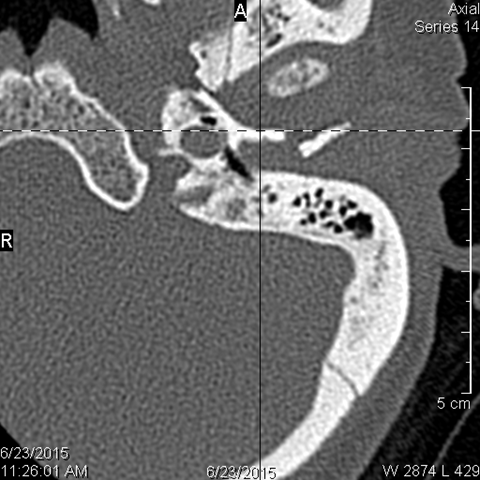

The condylar head and fossa as well as the temporomandibular joint space are abnormal. [Yes/No]

There is condylar fracture either within or outside of the joint capsule, or with or without involvement of the articular surface of the condylar head. [Yes/No]

There is evidence of radiodense intra-articular osteochondral fragments. [Yes/No]

There is bony injury or displacement of the external auditory canal and/or other evidence of temporal bone injury. [Yes/No]